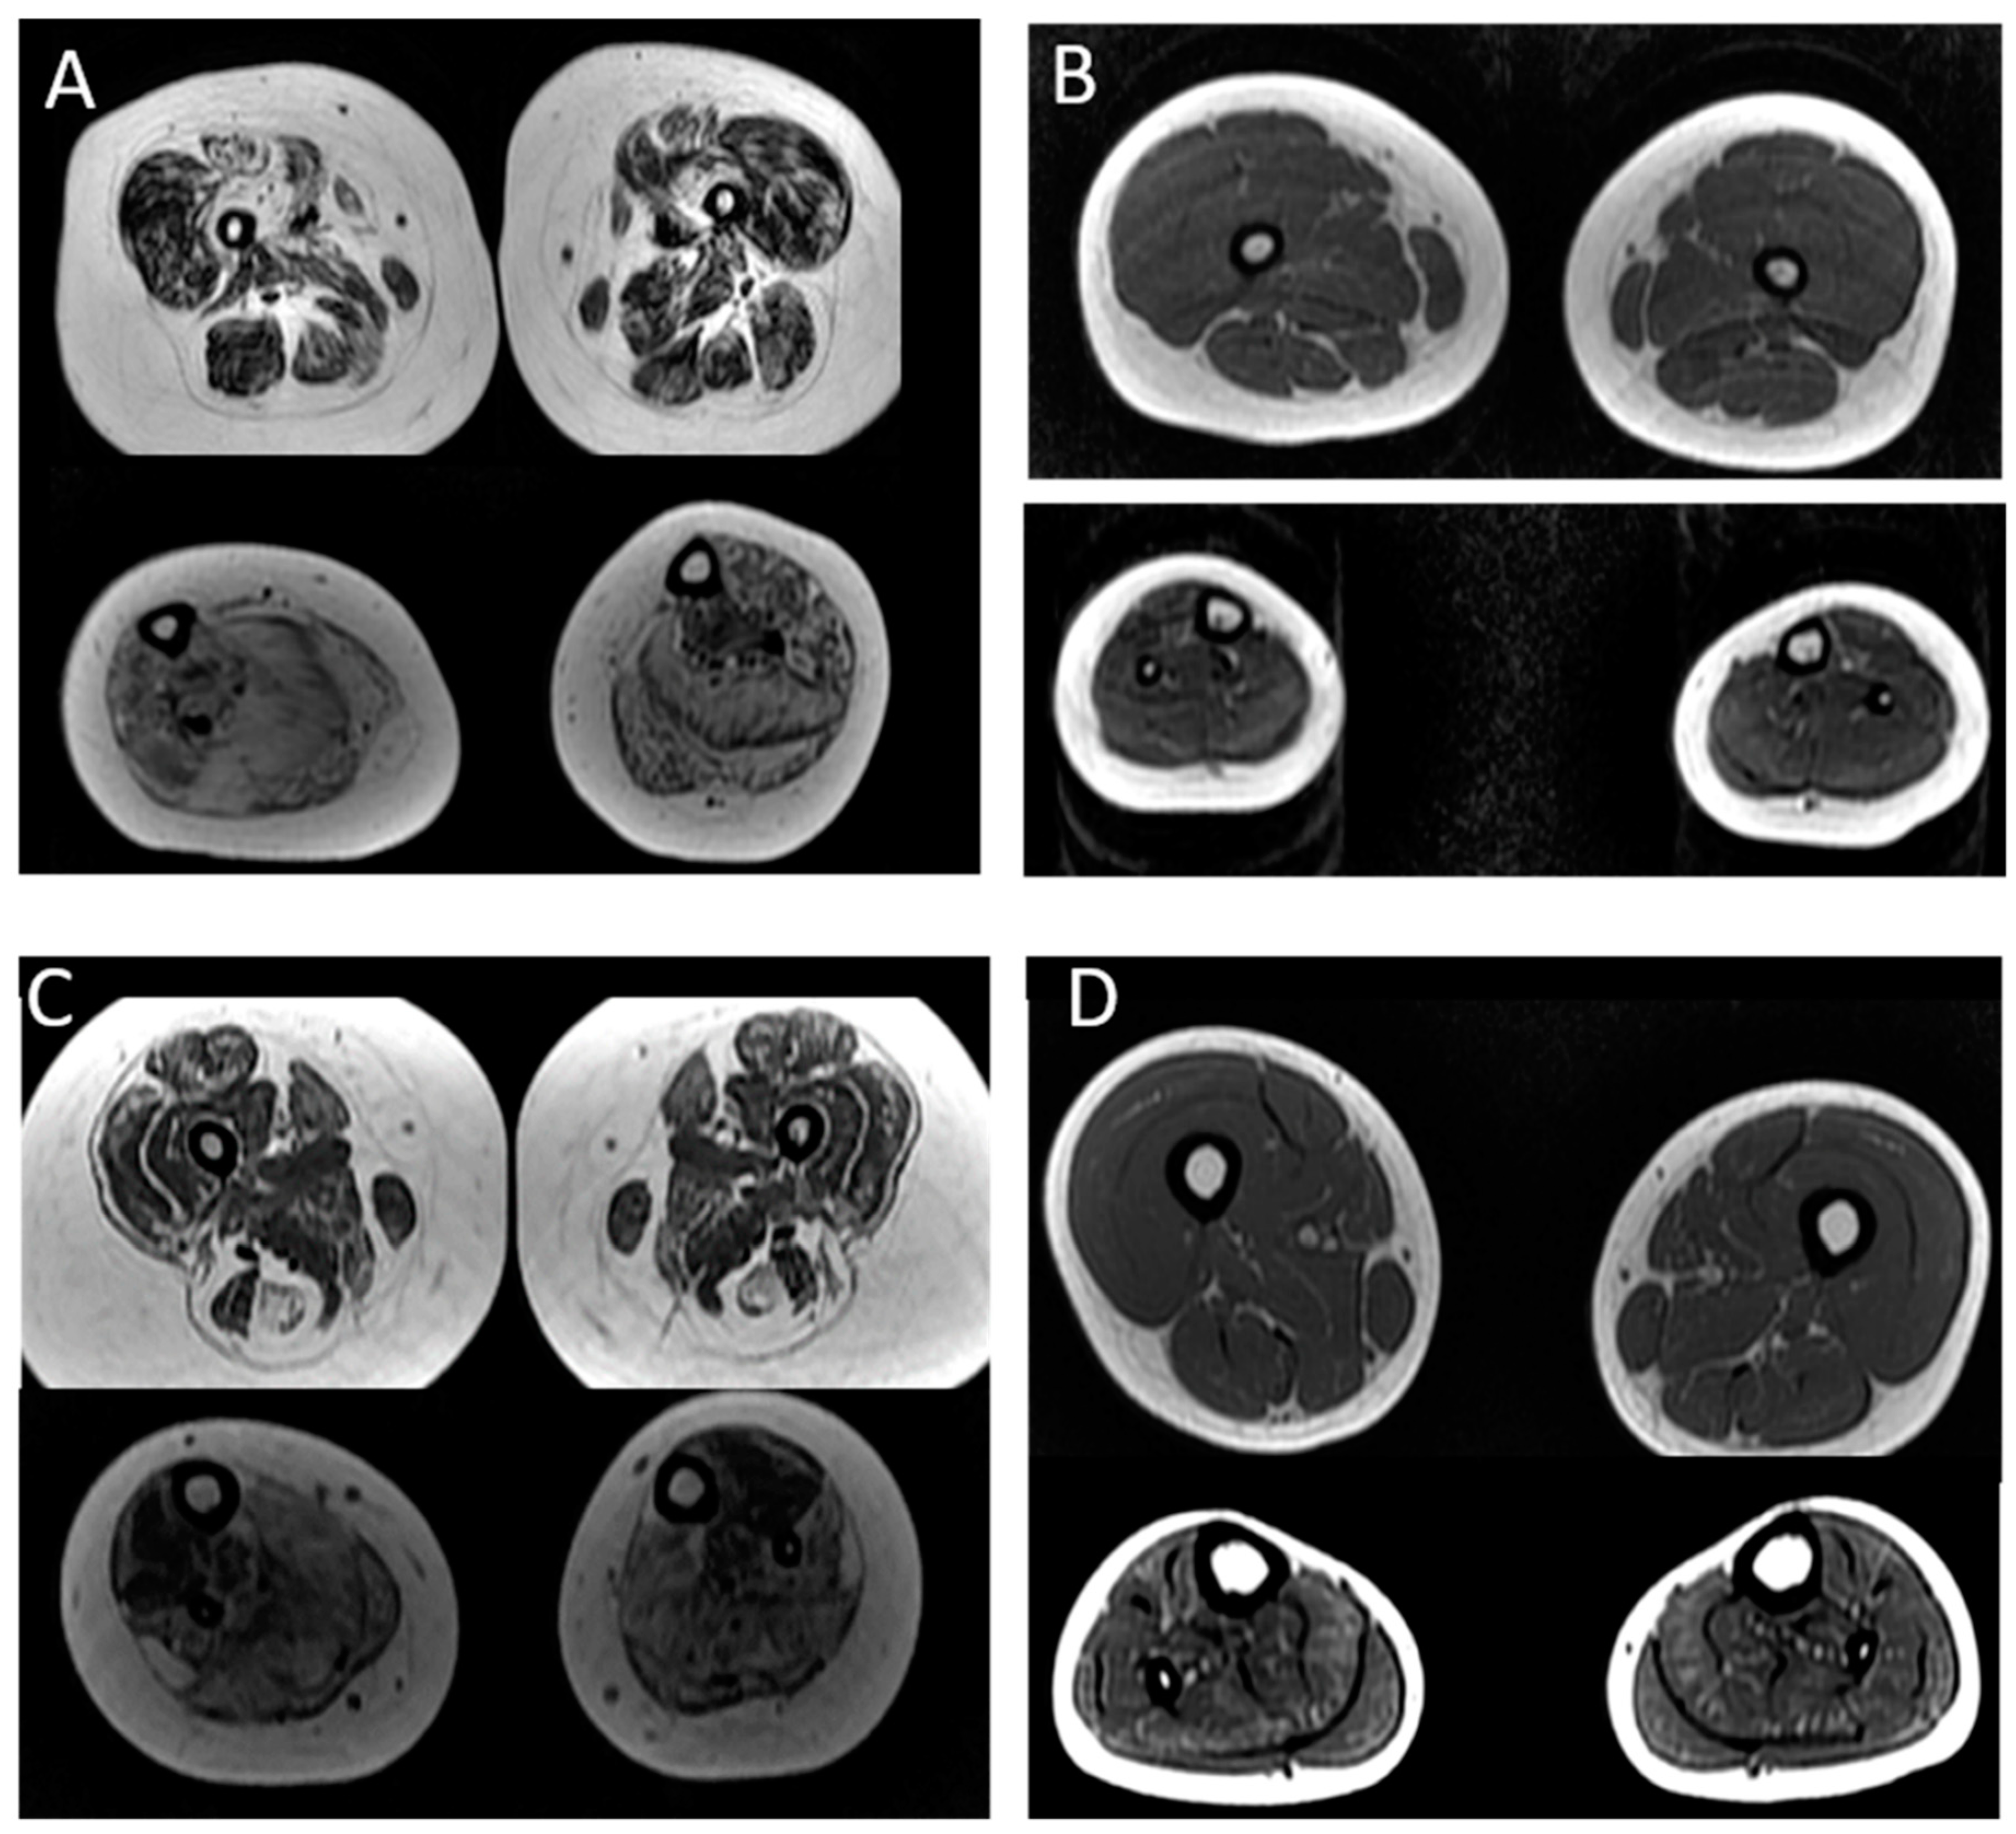

| Case | Age at Muscle MRI | Gene | Muscle MRI or CT (Mercuri Grade *) | |

|---|---|---|---|---|

| Thigh: | Legs: | |||

| P2 | 4 years | ACTA1 | No involvement | Tibialis anterior muscle: grade IIa Soleus muscle: no involvement |

| P3 | 8 years | ACTA1 | Diffuse fat infiltration of thigh muscles: grade III Biceps femoris and vastus lateralis muscles: grade IIb | Diffuse fat infiltration: grade III Tibialis posterior muscle: grade IIb |

| P6 | 12 years | TPM2 | Vastus lateralis and rectus femoris muscles: grade I OBS: Axial T1 image of the head: Involvement of temporal, masseter and pterygoid lateral muscles: grade II | Soleus muscle: grade IIb Gastrocnemius muscle: grade IIa |

| P7 | 13 years | TPM3 | Sartorius muscle: grade IIb Adductor magnus muscle: grade IIa Hamstring muscles: grade I | Soleus muscles: grade I Gastrocnemius muscle: grade I Tibialis anterior muscle: grade IIb Tibialis posterior muscle: grade IIb |

| P14 | 17 years | NEB | Diffuse fat infiltration of thigh muscles: grade I | Tibialis anterior muscle: grade III Soleus muscle: grade IIa |

| P15 | 15 years | NEB | Diffuse fat infiltration of thigh muscles: grade I | Tibialis anterior muscle: grade IIa Soleus muscle: grade IIb Fibular muscle: grade IIa |

| P16 | 17 years | NEB | Adductor longus muscle: grade III Adductor magnus muscle: grade III Rectus femoris muscle: grade IIa Vastus lateralis muscle: grade IIa | Tibialis anterior muscle: grade IV Soleus muscle: grade IV Fibular muscle: grade IV |

| P17 | 14 years | NEB | Diffuse fat infiltration of thigh muscles: grade I | Tibialis anterior muscle: grade II Soleus muscle: grade II Fibular. muscle: grade II |

| P21 | 7 years | NEB | Adductor longus muscle: grade I Adductor magnus muscle: grade IIb Rectus femoris muscle: grade IIb Vastus lateralis muscle: grade IIb | Tibialis anterior muscle: grade IIa Tibialis posterior muscle: grade IIa Soleus muscle: grade III Gastrocnemius muscle: grade III Fibular muscle: grade III |